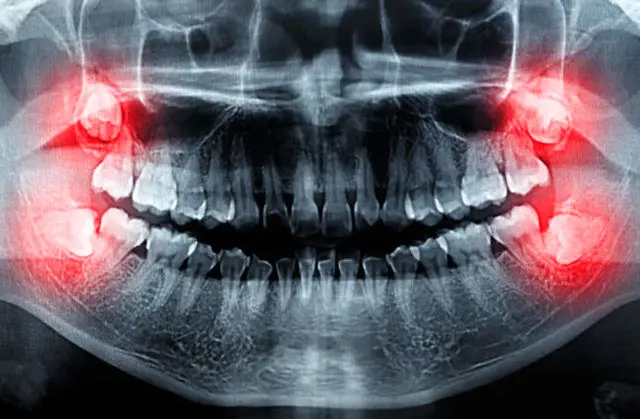

در این مطلب میتوانید معجزات پزشکی را در قالب تصاویر اشعه ایکس مشاهده کنید. آیا میتوانید باور کنید که این افراد جان…

عمل جراحی برای کشیدن دندان عقل یکی از رایجترین جراحیهای دندان است که برای بهبودی تا دو هفته فرصت نیاز داشته و مراقبت…